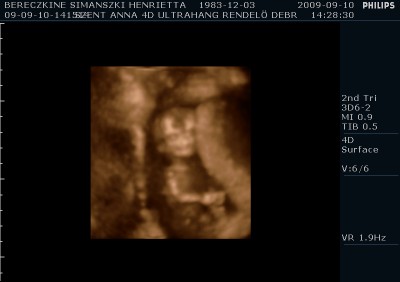

Megjöttem én is ismét, tettem fel képeket. A párom ragaszkodott hozzá, hogy kérjünk DVD-t, így hát átkapcsoltak 4D-be is. Kb. 10-15 perc lett a dvd, nagyon jópofa, látszik mindene. Mozognom, köhögnöm kellett nekem is, hogy a baba felébredjen, de amikor ébren volt, hihetetlen mit művelt. Egyik helyről a másikra átment, az első képen épp ez látható. :-) Ott a lábai vannak alul, a térdei nagyon jól látszanak. Épp ekkor rúgta át magát egy neki kényelmesebb pozícióba. :-)

A második képet meg csak azért tettem fel, hogy ez is legyen, de majd próbálok még a filmből kiszedni jobb képeket. Ezeket a párom csinálta 2 perc alatt.

Egyébként nálunk is megszólalt a nő, hogy nagyon fiúnak tűnik, de a párom rászólt, hogy ő nem akarja tudni. :D

Ami még érdekes, hogy tegnap 49mm-nek mérték, ma pedig 55mm-nek a CRL-t. A nyaki redő tegnap 1,4mm volt, ma az 1,3mm lett, itt nem nagy a különbség.

Hát lányok, nem bántam meg a DVD-t egyáltalán, bár még néhány hét múlva akartam csak megcsináltatni.